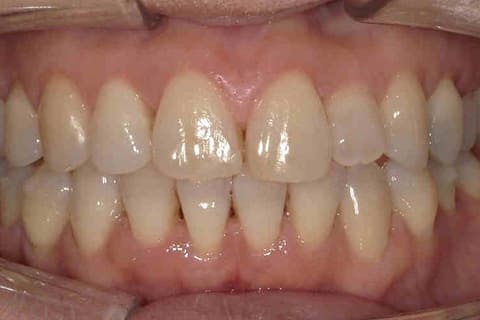

健康に美しく臨床実績集

虫歯や歯周病、事故などでの欠損、

噛めるようになりたい、見た目の美しさの追求など、

審美的に機能的に回復した治療経過報告症例です。